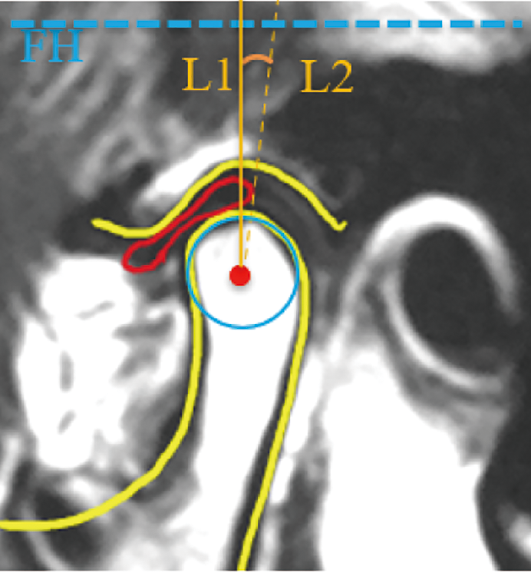

目的 分析颞下颌关节盘形态、位置与下颌骨垂直向和矢状向形态的关系。方法 选择因颞下颌关节紊乱综合征(temporomandibular disorders,TMD)就诊于四川大学华西口腔医院颞下颌关节科的223例成年女性患者。根据核磁共振影像(magnetic resonance imaging, MRI)将关节盘位置分为盘髁关系正常、可复性盘前移(disc displacement with reduction, DDwR)和不可复性盘前移(disc displacement without reduction, DDwoR) 3组,关节盘形态分为基本正常和异常两组。根据头颅侧位片测量下颌骨垂直向(下颌平面角、Y轴角、下颌支高度)和矢状向(SNB、下颌体长度、鞍角)形态指标。比较各个测量指标与关节盘位置、形态的相关性。结果 关节盘位置和形态与下颌平面角、下颌支高度和Y轴角之间具有相关性(P<0.05),左侧关节盘位置与SNB之间具有相关性(P<0.05),双侧关节盘形态与SNB之间具有相关性(P<0.05)。结论 关节盘的形态和位置与下颌骨的垂直向和矢状向形态之间有相关性,与垂直向形态之间的相关性更加密切。

Objective To analyze the relationship between the morphology and position of the temporomandibular joint disc and the vertical and sagittal morphology of the mandible. Methods A group of adult female patients with temporomandibular disorders were selected in the Department of Temporomandibular joint at West China Stomatological Hospital, Sichuan University. They were classified into normal position, disc displacement with reduction (DDwR), and disc displacement without reduction (DDwoR). The total number of patients included in this study was 223. The morphology of the disc was classified into normal and abnormal groups. Vertical (mandibular plane angle, Y-axis angle, ramus height) and sagittal (SNB, mandibular body length, saddle angle) morphological indicators of the mandible were measured on the lateral cephalometric radiographs. The correlation between the indicators and the morphology and position of the disc was compared. Results It showed that there was a correlation between the position and morphology of the disc and mandibular plane angle, Y-axis angle and ramus height (P<0.05), a correlation between the position of the left disc and SNB (P<0.05), and a correlation between the morphology of the bilateral disc and SNB (P<0.05). Conclusion There is a correlation between the morphology and position of the disc and the vertical and sagittal mandibular morphology, with a closer correlation with the vertical shape.